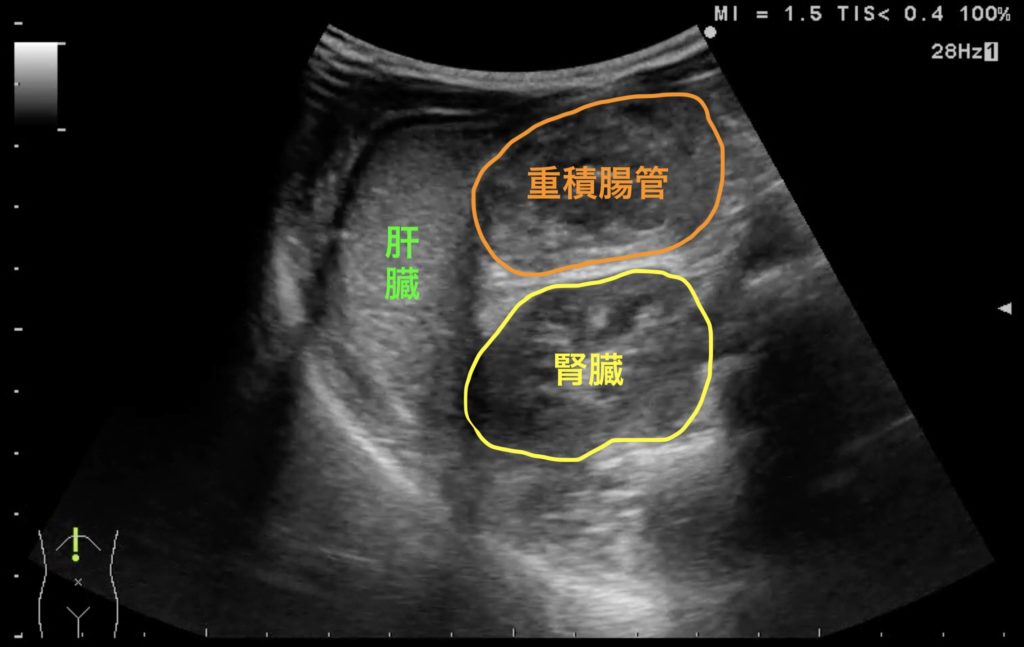

【#24】救急外来。不機嫌な幼児。考えられる疾患はなにか?

腸重積

小児の腹痛や機嫌不良の鑑別疾患に腸重積があるが、熟練した医師による超音波の診断精度はきわめて高いとされる。腸重積でみられる所見には、Doughnut signやPseudo-kidney signがあるが、上の図でもそれらが確認できる。腎臓を同時に描出することで、重積した腸管を腎臓と見誤る懸念をなくすことができる。